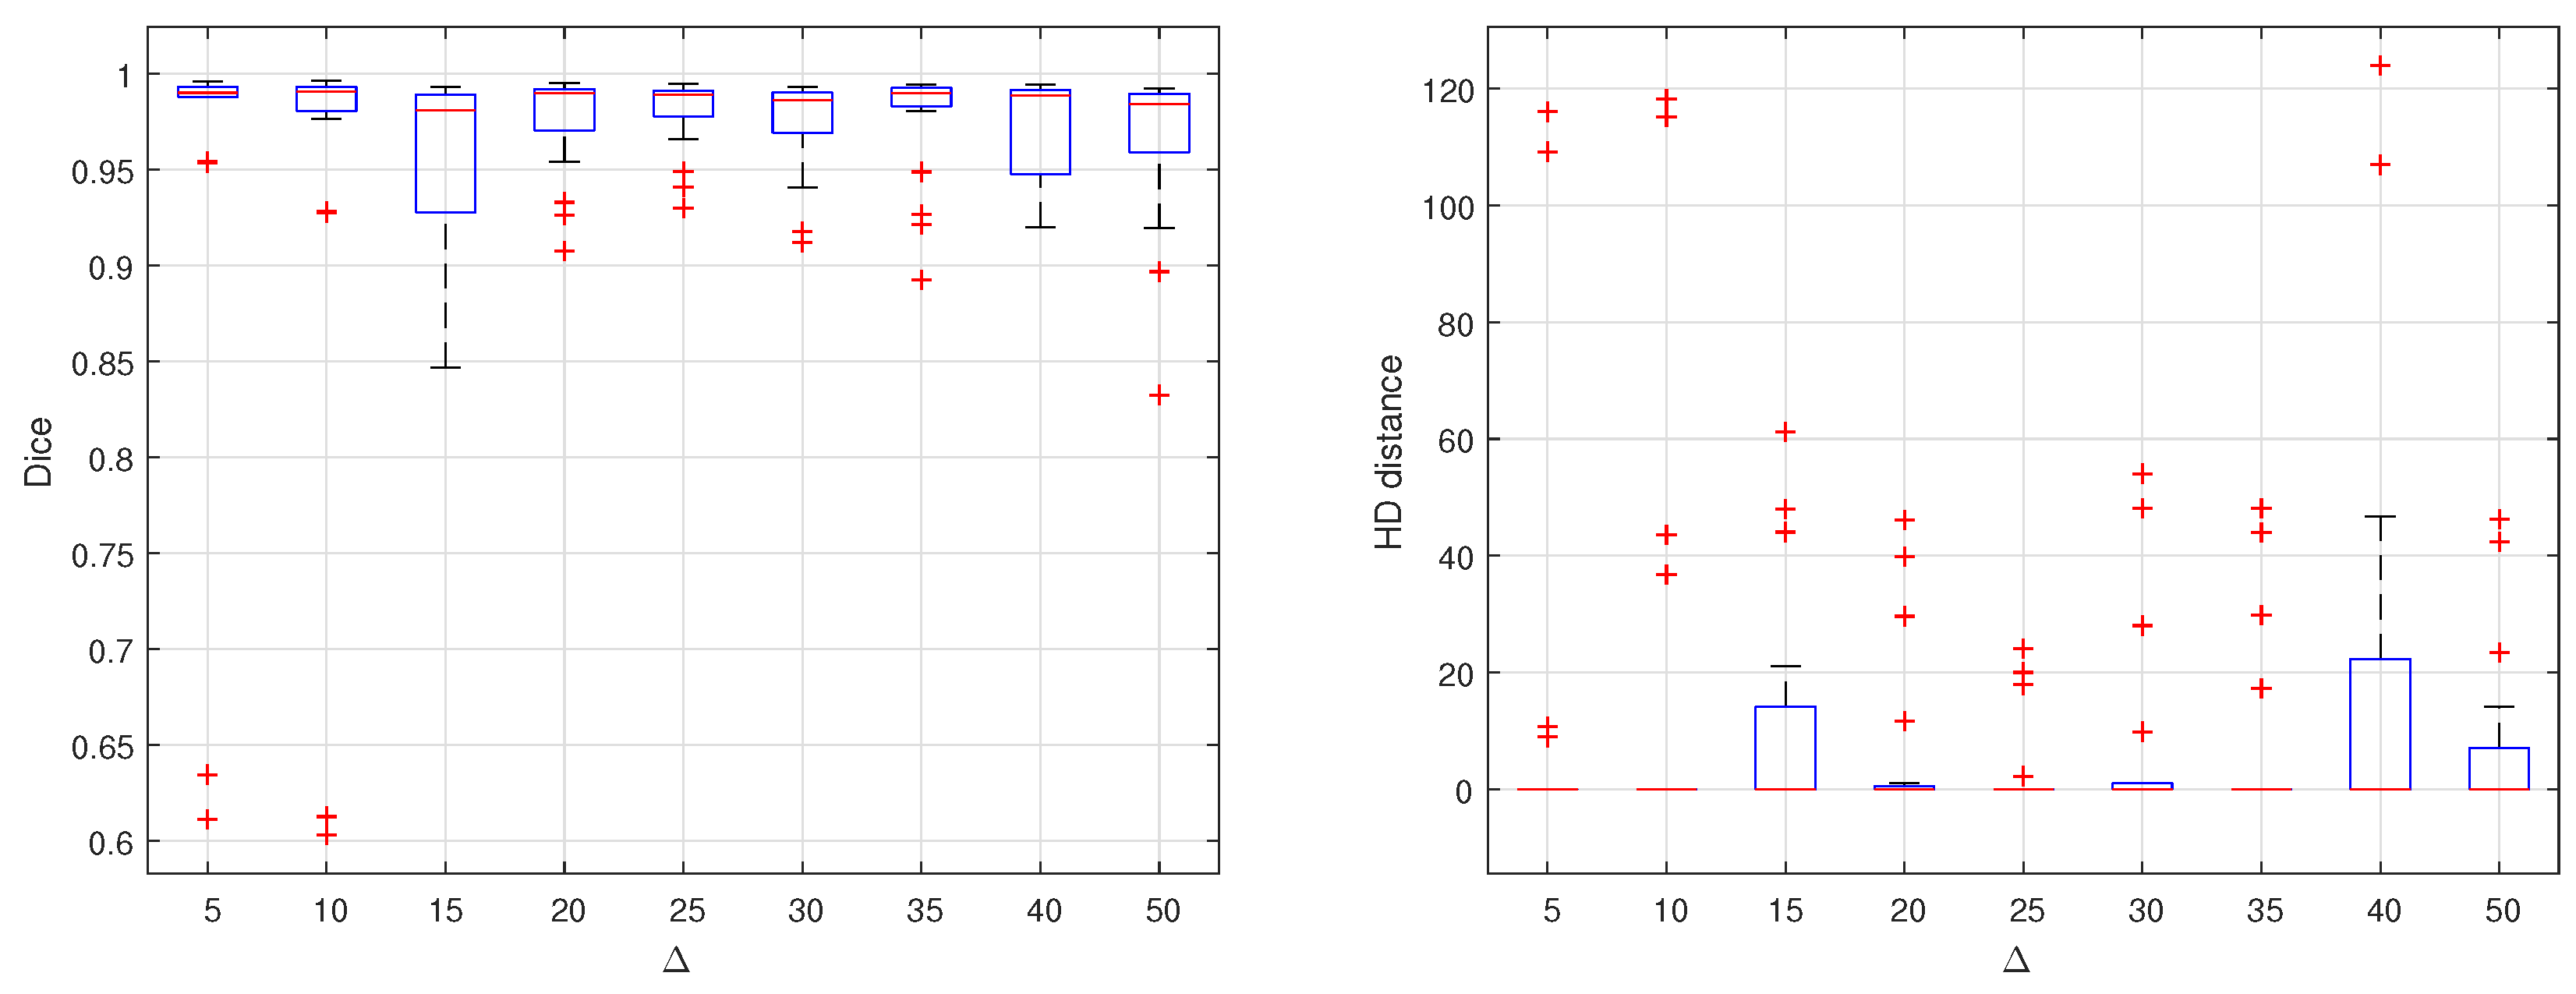

3.2. Fused Image Construction

3.3. Overall Segmentation Evaluation